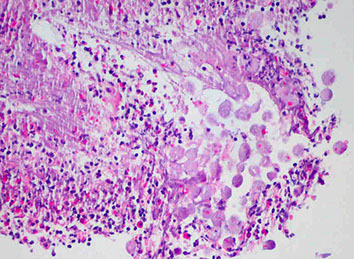

Microscopic pathology of Crohn disease. A, Haphazard crypt organization results from repeated injury and regeneration. B, Noncasearing granuloma. C, Transmural Crohn disease with submucosal and serosal granulomas (arrows)

Microscopically, Crohn disease is characterized by transmural inflammation. Here, inflammatory cells (the bluish infiltrates) extend from mucosa through submucosa and muscularis and appear as nodular infiltrates on the serosal surface adjacent to fat. Note the granulomatous inflammation.